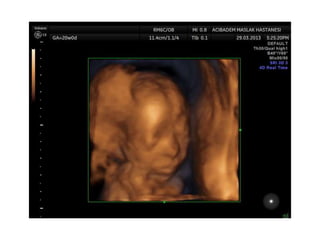

Binder Phenotype

a flat profile and depressed nasal bridge.

Short nose, short columella, flat naso-labial angle and

perialar flattening

Isolated Binder Phenotype transmission would be

autosomal dominant

Binder Phenotype can also be an important sign of

chondrodysplasia punctata (CDDP)